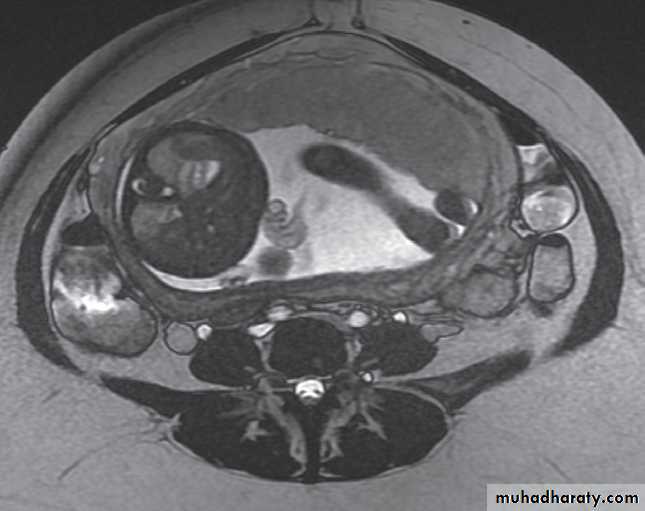

Magnetic resonance imaging is useful to determine the extent of carcinoma of the cervix preoperatively, because the extent (or tumour stage) determines whether the patient is managed with surgery or with chemoradiotherapy.

The observations to be made are whether the tumour is confined to the cervix .

It extends into the parametrium, lymph nodes, rectum, bladder or pelvic side walls .